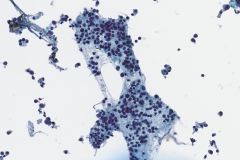

Specimen Type: FNA of Station 7 Lymph node, Diff-Quik and Papanicolaou Stained smears, ThinPrep® Non-Gyn cytology, Formalin-Fixed Cell Block

Cytologic Diagnosis: Positive for Malignant Cells, Metastatic Carcinoma of Breast Origin. The malignant cells are positive for GATA3, AE1/AE3 and estrogen receptor. P40, TTF-1 and Napsin A are negative.

Biopsy / Pathologic Diagnosis: Metastatic Adenocarcinoma consistent with patient’s known history of a breast cancer primary. Immunohistochemical stains including a GATA3 and TTF-1 were used in evaluation of this material. The neoplastic cells show strong and diffuse expression of GATA3 and are negative for expression of TTF-1, supporting a metastasis from the patient’s known breast primary. Immunohistochemical stains for estrogen receptor and progesterone receptor were both positive and HER2 was negative.

Ductal breast carcinoma specimens are highly cellular and consist of a variety of cell arrangements. The cells will commonly be seen as poorly cohesive clusters, some isolated single cells, and rare sheets of cells. These specimens will have enlarged and hyperchromatic nuclei that are eccentrically placed and often protruding from the cytoplasm. The chromatin has a bland appearance, ranging from finely to coarsely granular, with prominent, irregularly shaped nucleoli. Myoepithelial cells sitting on top of or lining the ductal breast cells are helpful in determining if the specimen is benign and should not be present in IDC specimens. The background of IDC is usually clean, but inflammation, blood, and granular debris may be observed.1,14 Immunohistochemistry (IHC) markers that can be used to stain for ductal breast carcinoma are Ki-67, p63, CK5/6, ER, Mammaglobin, GCDFP-15, E-Cadherin and GATA3. Double staining for cytokeratin, smooth muscle myosin heavy chain, Calponin, and/or p63 is helpful for determining if myoepithelial cells are present in the specimen.1,15 In the current case study, the patient’s specimen presented with marked cellularity consisting of a population of both 3-dimensional clusters of cells and many dyshesive single cells. In the smaller 3-dimensional clusters, some of the cells can be seen forming glandular structures and some look as if they are molded together. The nuclei are enlarged, eccentrically placed, and have a mix of both smooth and irregular nuclear contours. The cells all have high N/C ratios and there is a moderate amount of anisonucleosis. The chromatin has a predominantly hyperchromatic appearance, is finely granular and large prominent nucleoli can be observed. The cytoplasm is scant, has well-defined cytoplasmic borders, and is finely vacuolated. Mucinous vacuoles in the cytoplasm can be seen in the larger 3-dimensional clusters of cells. Crush artifact and necrosis can be observed in the background.